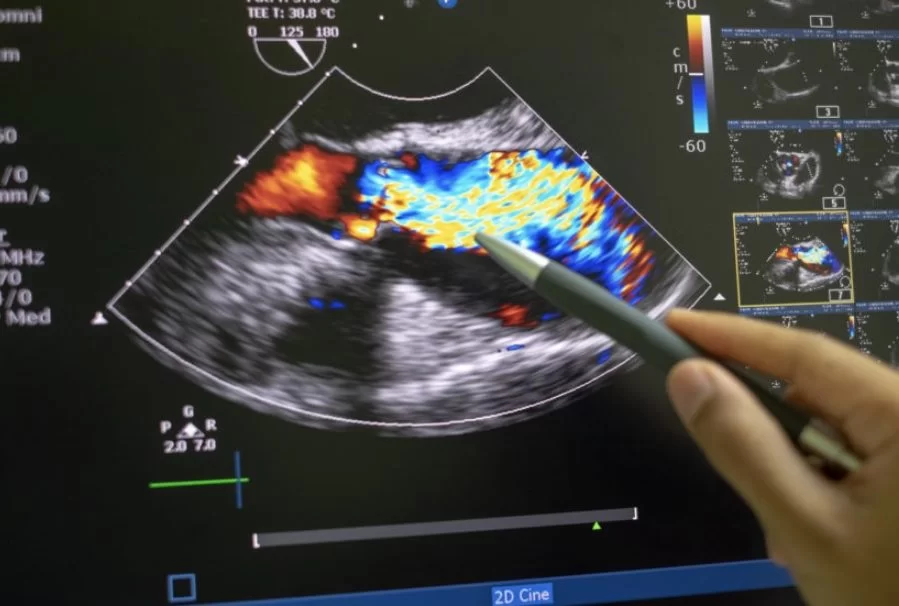

- Doppler Colorido: O exame combina o Doppler colorido, que codifica a direção e a velocidade do fluxo sanguíneo em diferentes cores, com o ultrassom tradicional, permitindo uma visualização detalhada do fluxo sanguíneo.

- Interpretação dos Resultados: O médico especialista analisa as imagens para detectar anomalias no fluxo sanguíneo, como turbulências ou bloqueios, e para medir o diâmetro da aorta e das artérias ilíacas.